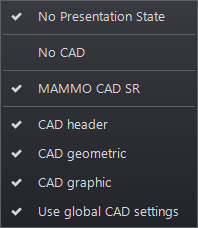

Ha a vizsgálat CAD mutatót tartalmaz, a prezentációs állapot ikon (kiemelve) megjelenik a kép bal felső sarkában, ha az egy képkockában jelenik meg.

A prezentációs állapot ikon kiválasztásakor megjelenik egy lenyíló menü, amely az aktuális prezentációs állapot funkciókból áll (megjelenítés vagy elrejtés):

Alkalmazásuk esetén ezek a funkciók a képkocka prezentációs állapot eszközével felülírják az egyes képekre alkalmazott aktuális CAD mutató prezentációs állapott. Ha mammográfia CAD ábra és geometriai overlayek vannak egy képhez, a listából válassza ki a megfelelő opciót, és csak egy képre alkalmazza ezt az opciót.

| Funkció | Leírás |

| CAD fejléc | A támogatott gyártókat és rendszereket jelölő fejléc a képen |

| CAD ábra | CAD mutató fejléc és csak grafikus overlayek jelennek meg minden képen. Akkor érhető el, ha grafikus és geometriai overlayek is vannak |

| CAD geometria | CAD mutató fejléc és csak geometriai overlayek jelennek meg minden képen. Akkor érhető el, ha grafikus és geometriai overlayek is vannak |

Az alapértelmezett CAD overlay beállítások a Mammográfiás CAD alatt található Eszközök/Mammo menüben konfigurálhatók.